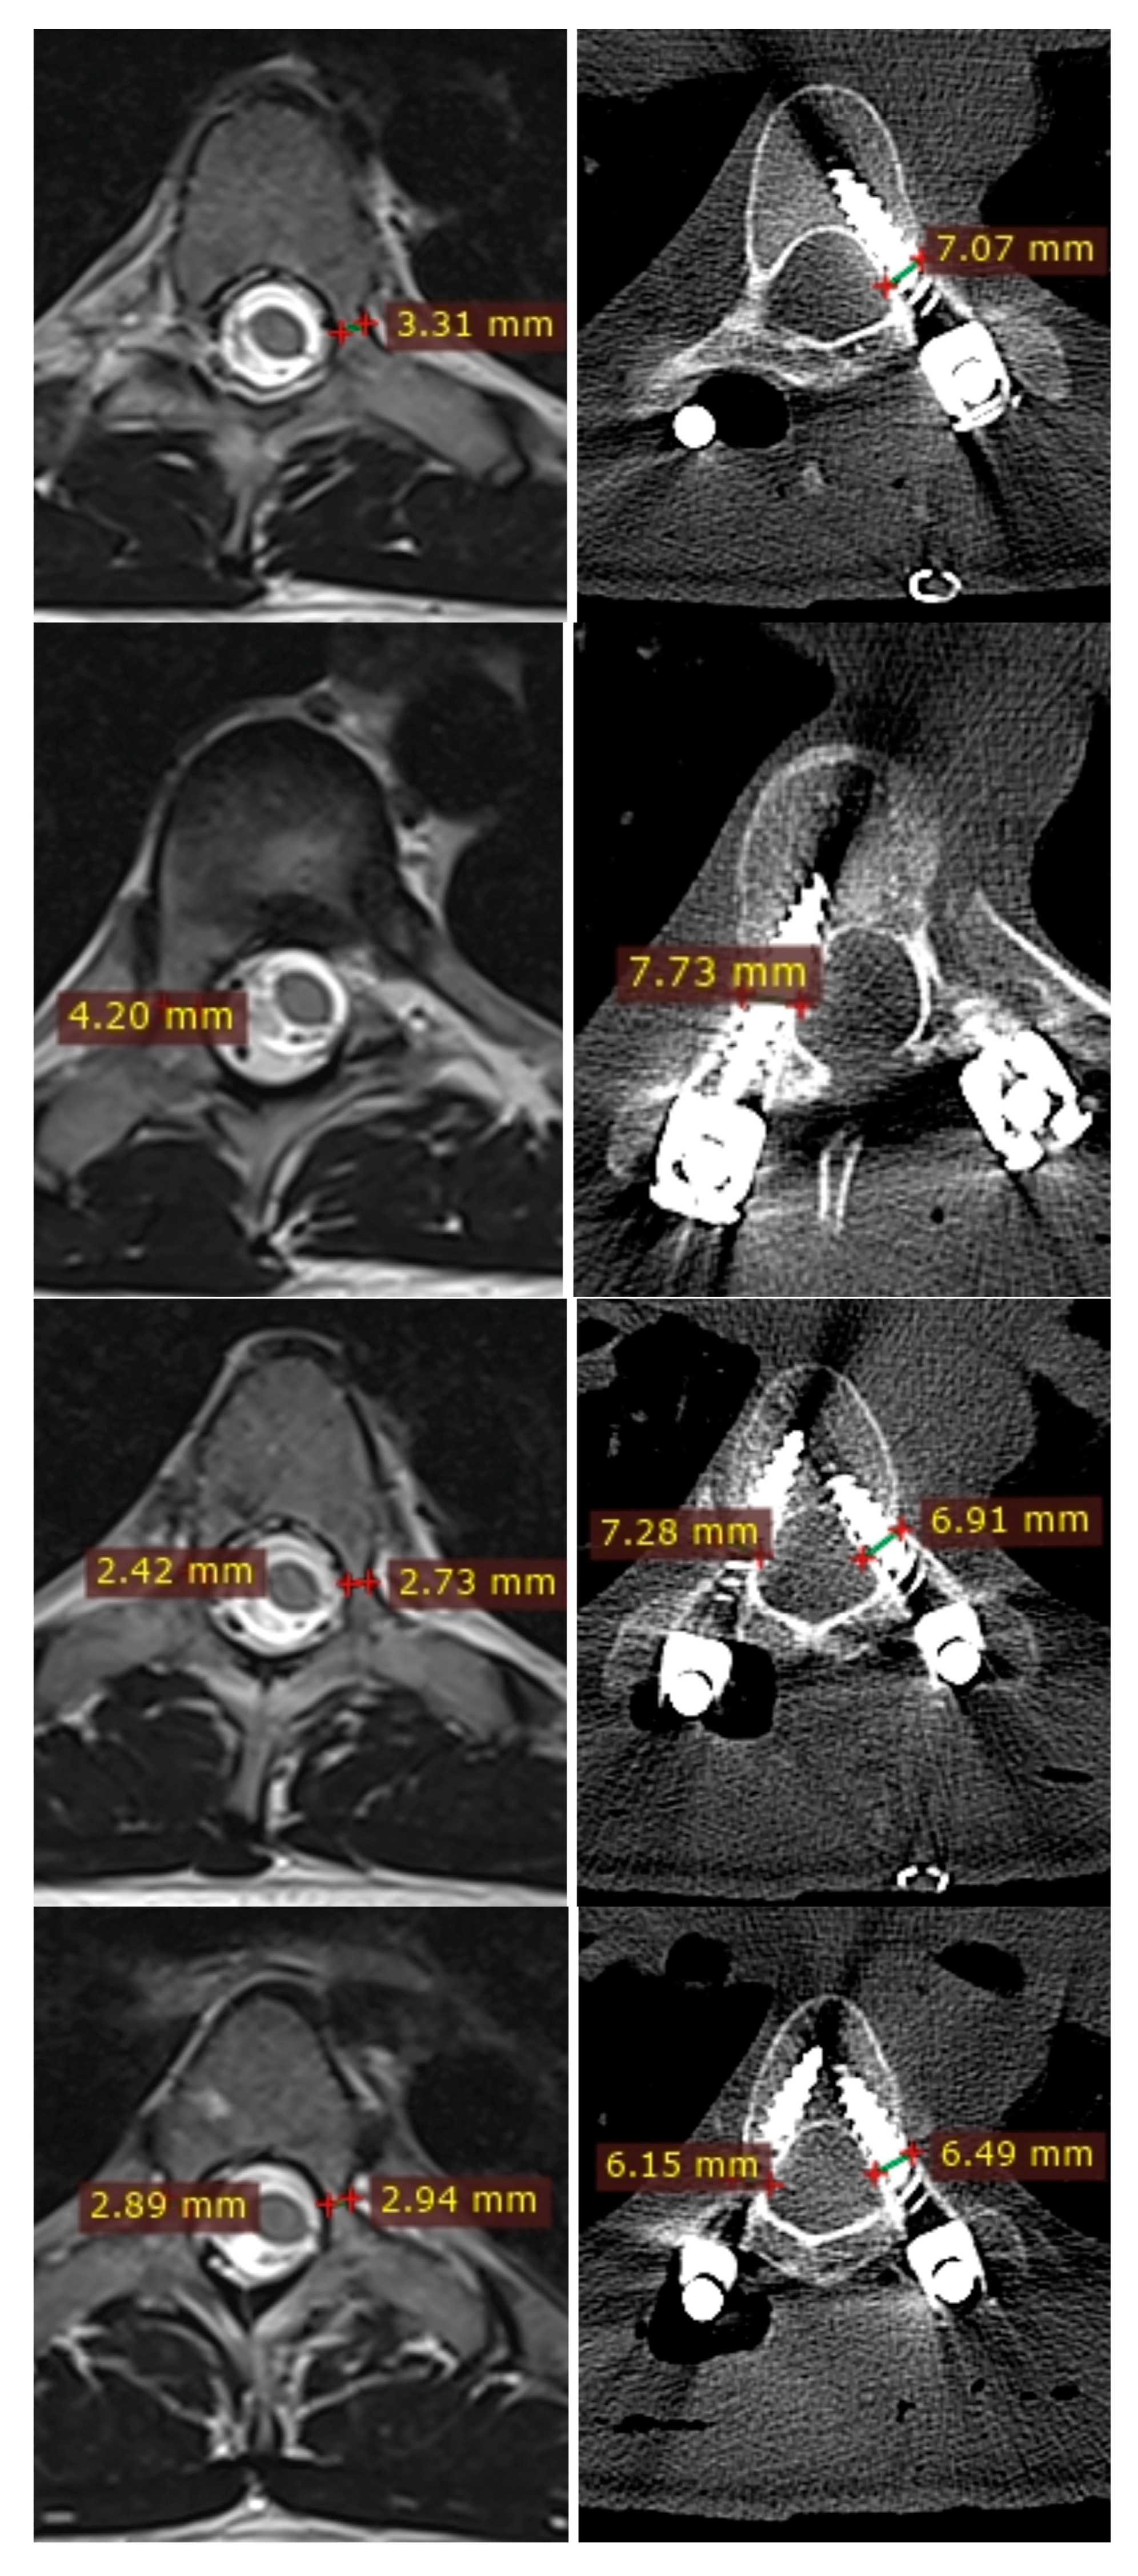

2.3. Radiographic Parameters